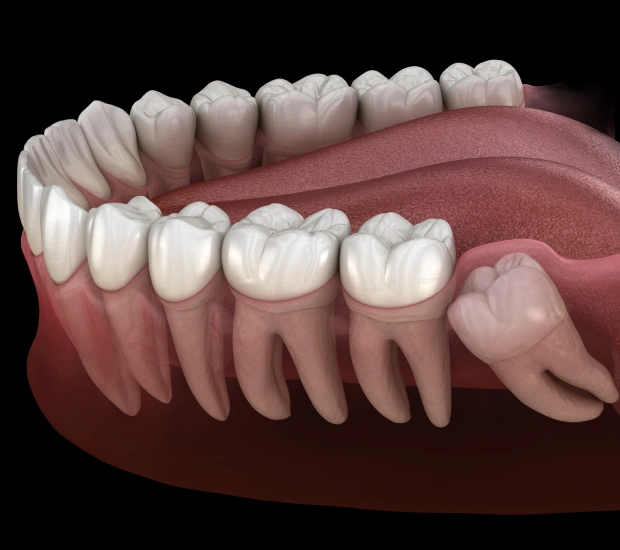

Wisdom teeth, or third molars, often don’t have enough space to grow properly—leading to pain, swelling, and potential complications. At Batavia Dental, we provide gentle, precise wisdom teeth removal in St. Charles, IL to protect your oral health and prevent future issues.

Why Wisdom Teeth Removal May Be Necessary

- Impacted wisdom teeth (trapped beneath the gums)

- Damage to nearby teeth

- Overcrowding or shifting of teeth